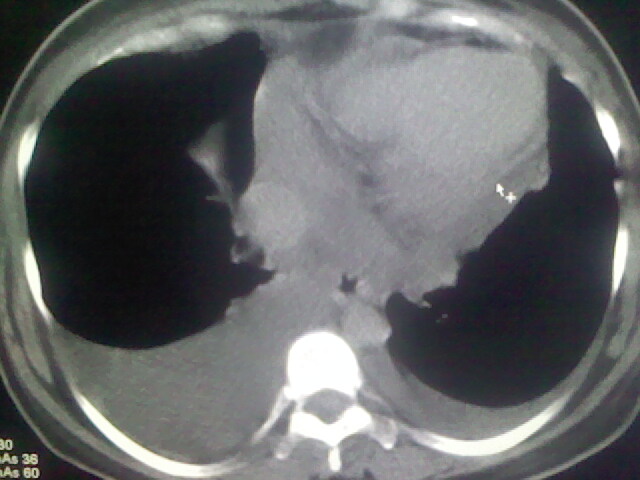

女,24,剖腹产后,突觉胸痛,干咳,不能平卧

双肺“肺泡性肺水肿” “胸腔积液”!

考虑肺梗塞、肺水肿,双侧胸腔积液

肝脾大,双侧胸腔积液,双肺水肿,肺动脉[包括远端小动脉],左右心房,左心室增宽,右心室主动脉无明显改变,符合左心功能不全征;;建议除外二尖瓣关闭不全,扩张性心肌病

考虑产后心肌病,心功能不全,肺水肿,双侧胸腔积液。